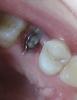

JUl_al Опубликовано 19 мая, 2011 Поделиться Опубликовано 19 мая, 2011 Доброго времени суток! Так, начну с того, что 16 мая мне удалили сразу 2 пятерки на верхнем ряду. Все прошло безболезненно, да и 4-й день уже - боли никакой нет и не было, опухоли тоже нет, но смущает что-то светлое внутри лунки. Что это? не воспаление ли? Ссылка на комментарий

Bier Опубликовано 19 мая, 2011 Поделиться Опубликовано 19 мая, 2011 это фибрин. Так и должно быть. Все хорошо. Ссылка на комментарий